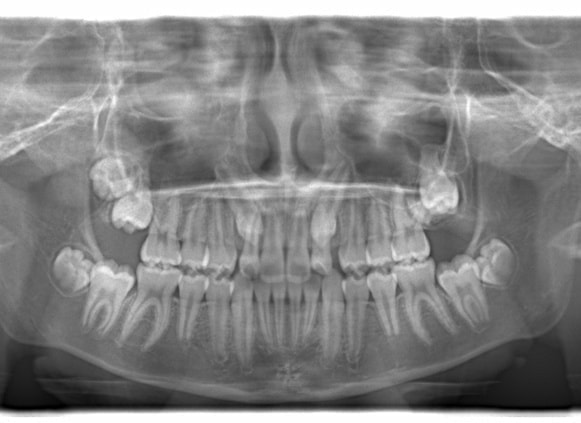

小児期ケース:反対咬合+上顎両側3番埋伏歯

(受け口+3番目の永久歯が左右両方とも埋まってしまい、はえてこない)

治療法:上顎急速拡大装置+クリアスナップ+フェイスマスク+上顎3番は開窓牽引CT写真にて位置確認

治療前

FX(フェイシャルアキシス)は85度なので東洋人の平均値に近く、下顎が前方に過剰成長するリスクは強くはありません。

しかしやはり上顎は劣成長で、下顎が優位な状態ではあります。

上下顎のギャップはありますが、顔面自体の幅径は良好な値を示していますので、スペース不足は拡大することによって解決できポテンシャルはあると考えられます。

左右の非対称もさほど強くありません。

骨年齢は実年齢よりも低めなので、今後下顎の旺盛な成長が見込まれます。

検査時のレントゲン分析では、上下顎の関係は、上顎の劣成長があり下顎前突傾向という値がでておりましたが、前歯ジャンプ後はフェイスマスクの効果もあり、上下顎の関係は正常化しています。

上顎が若干優位になっていますので、今後の下顎の成長のための貯金になっているくらいです。